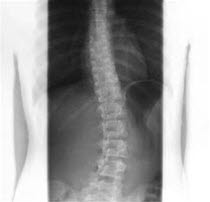

Små skjevheter i ryggsøylen er svært vanlig og gir som regel lite problemer. Ved skoliose er skjevhetene imidlertid så store at de kan gi problemer. Sett bakfra kan ryggen ha en S-form eller en C-form.

Diagnosen stilles vanligvis på bakgrunn av typisk sykehistorie, legeundersøkelse og eventuelt røntgenbilder av ryggsøylen.

Den enkleste metoden er å be barnet/tenåringen bøye seg fremover. Sett bakfra vil man da tydelig kunne se skjevheten. Forandringene er oftest i brystdelen av ryggen, men de kan også forekomme i korsryggen, eller i overgangen mellom de to områdene. Påvises en slik skjevhet, vil legen henvise til røntgen. Røntgenbilder brukes til å beregne den såkalte Cobbs vinkel, som er et viktig objektivt mål for grad av skjevhet. Dersom røntgenbildene bekrefter skoliose, henvises barnet som regel til spesialist i barnemedisin eller ortopedi. Alle barn under 10 år som har fått påvist skoliose anbefales henvisning direkte til vurdering ved Oslo universitetssykehus, Rikshospitalet (Nasjonal behandlingstjeneste for barneskoliose).